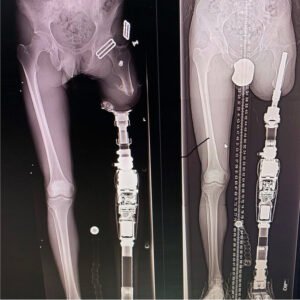

هنا تقدم تقنية الاندماج العظمي (Osseointegration) حلا مختلفاً جذرياً: طَرف صناعي يُثبت مباشرة في العظم ذاته، يعبر الجلد عبر فتحة جراحية دقيقة، ويُلغي الحاجة إلى السوكت إلى الأبد. هذ ليس تطور للسوكت بل هو اختلاف جذري في طريقة استخدام الطرف الصناعي.

تقنية جراحية متطورة يتم فيها زرع “مسمار” معدني (عادة من التيتانيوم) مباشرة داخل العظم، ليبرز جزء منه خارج الجلد ويتم تركيب الطرف عليه مباشرة.

- المرحلة الأولى: زرع الوتد داخل العظم وإغلاق الجرح فوقه ليتم الالتحام (يستغرق 3-6 أشهر).

- المرحلة الثانية: فتح ثقب صغير في الجلد لتركيب القطعة التي سيتم ربط الطرف بها.